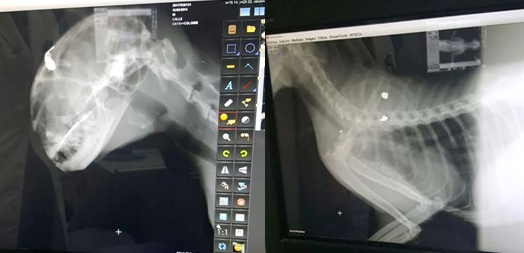

El animal, ha denunciado Cacma, apareció en un descampado herido de muerte con tres perdigones, uno de ellos en la cabeza. Tuvo que ser sacrificado por el veterinario

Según relata Cacma, que ha publicado imágenes de gran crudeza, en la tarde de ayer lunes apareció un gato agonizante en un descampado cercano a la barriada Marismas del Odiel de la capital. El felino, que "estaba aferrándose a la vida sin ni siquiera poder mover apenas más que el rabo", fue trasladado inmediatamente a un centro veterinario en el cual, tras "certificar que había recibido tres disparos con un arma de perdigones, dos en el pecho y uno profundo en el cráneo, recomendaron la eutanasia humanitaria para acabar con su larga agonía".